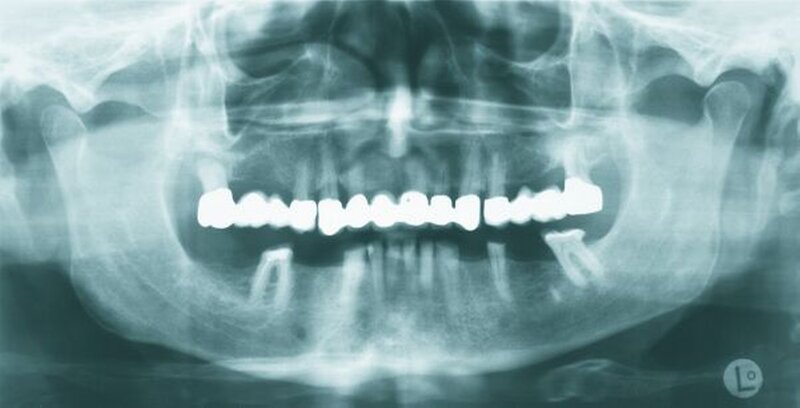

Auf dem vor Anfertigung des Zahnersatzes angefertigten OPG sowie den angefertigten Zahnfilmen der regiones 17 und 27 waren generalisierte horizontale Knochenverluste im Bereich aller verbliebenen Zähne erkennbar. Die Zähne 17 und 27 wiesen zudem vertikale Knocheneinbrüche auf. Eine radiologische Furkationsbeteiligung ließ sich in beiden Fällen nachweisen. Der Zahn 47 war wurzelkanalgefüllt.

Obwohl der Zahn 47 eine radiologisch nicht vollständig bis zum radiologischen Apex reichende Wurzelfüllung aufwies, wurde auf eine Revision der Wurzelfüllung aufgrund einer seit mehr als 15 Jahren bestehenden Beschwerdefreiheit des Patienten und vollständiger Symptomlosigkeit des Zahnes verzichtet [Peak et al., 1994]. Der Patient wurde über diese Sachverhalte ausführlich aufgeklärt und erklärte sich mit dem Belassen der Wurzelfüllung einverstanden.